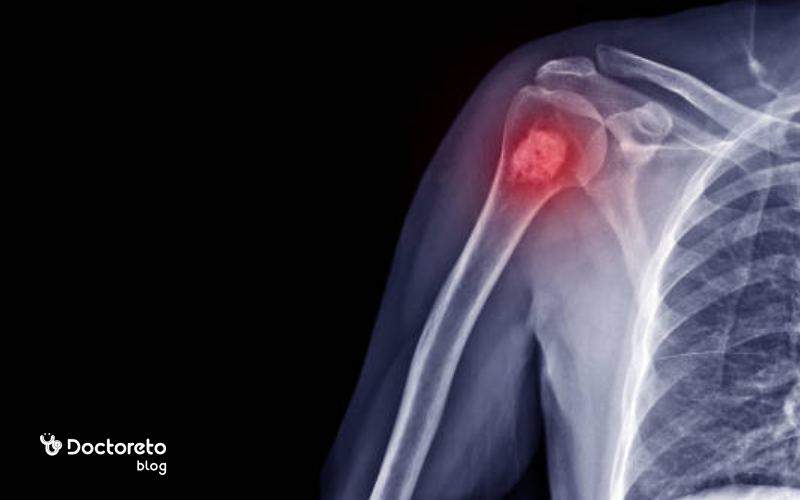

یکی از سوالات مهم برای بیماران و اطرافیان آنها این است که ایا سرطان مغز استخوان کشنده است؟ سرطان مغز استخوان که نوعی سرطان خون محسوب میشود و میتواند منجر به مشکلات جدی مانند ضعف استخوانها یا اختلال در کلیهها شود. خوشبختانه، با درمانهای امروزی، بسیاری از بیماران شانس خوبی برای زندگی طولانیتر دارند؛ به خصوص اگر زودتر تشخیص داده شود. اگر این بیماری نادیده گرفته شود، میتواند خطرناک باشد. پس، چه باید کرد؟ در ادامه این مطلب از دکترتو همراه ما باشید تا دقیقتر این موضوع را بررسی کنیم.

سرطان مغز استخوان ممکن است در موارد پیشرفته یا بدون درمان مناسب، کشنده باشد. این بیماری با تاثیر بر تولید سلولهای خونی سالم، عملکرد سیستم ایمنی را مختل میکند و در نتیجه بدن را در برابر عفونتها و خونریزیها آسیبپذیر میسازد. با این حال، پیشرفتهای چشمگیر در درمانهای نوین مانند پیوند مغز استخوان باعث شدهاند بسیاری از بیماران سالها با کیفیت زندگی مطلوبتری زندگی کنند. بنابراین، کشنده بودن این سرطان به نوع، مرحله و پاسخ بدن به درمان بستگی دارد.

سرطان مغز استخوان در مراحل اولیه معمولا کشنده نیست و در بسیاری از موارد با تشخیص بهموقع و شروع سریع درمان میتوان آن را کنترل یا حتی وارد مرحلهی بهبود کرد. در این مرحله، میزان گسترش سلولهای سرطانی هنوز محدود است و بدن بهتر به درمانهایی مانند شیمیدرمانی، داروهای هدفمند یا پیوند مغز استخوان پاسخ میدهد. به همین دلیل، شناسایی زودهنگام علائم و مراجعه به پزشک نقش مهمی در افزایش شانس بهبود و طول عمر بیمار دارد.

ایا سرطان مغز استخوان در مراحل پیشرفته کشنده است؟

سرطان مغز استخوان در مراحل پیشرفته میتواند کشنده باشد زیرا در این مرحله سلولهای سرطانی بهطور گسترده در بدن پخش شده و عملکرد مغز استخوان در تولید سلولهای خونی سالم بهشدت مختل میشود. این وضعیت باعث ضعف سیستم ایمنی، کمخونی شدید و مشکلات انعقادی میشود. با این حال، پیشرفت روشهای درمانی مانند پیوند مغز استخوان، داروهای هدفمند و ایمونوتراپی باعث شدهاند که حتی بیماران در مراحل پیشرفته هم بتوانند طول عمر بیشتری داشته و کیفیت زندگی بهتری تجربه کنند.